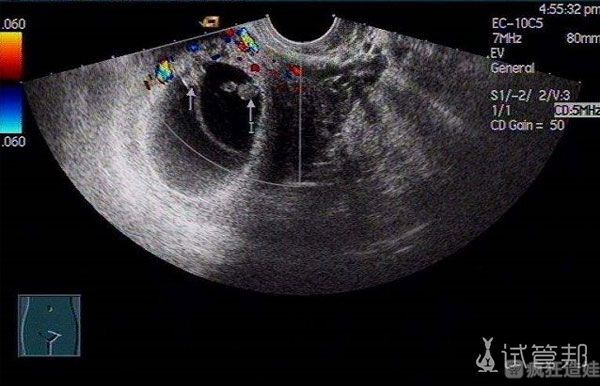

我的试管婴儿促排方案是长方案,时间花的要比短方案久一点,但听说获得的卵子质量会更高,好在就是多打一针。等待的时间长了些,过了半个月又是B超,又是查激素,听医生说直接启动,激动的不行,迫不及待想要早点完成这一切,和宝宝见面。说实话,取卵前一晚彻夜难眠,各种思绪涌上心头,难以平静下来入睡。轮到我取卵的时候,感觉也没那么紧张了,手术时间也不算太长,休息了片刻就出来了,得知取了16个卵子,瞬间活力满满,除了腹部有点轻微的胀。接下来就是难熬的3天等待结果过程,好怕受精失败,要重新来过。还好老天爷眷顾我,配了4个胚胎,放了1枚鲜胚,冷冻了一管胚胎,真的觉得自己很幸运。